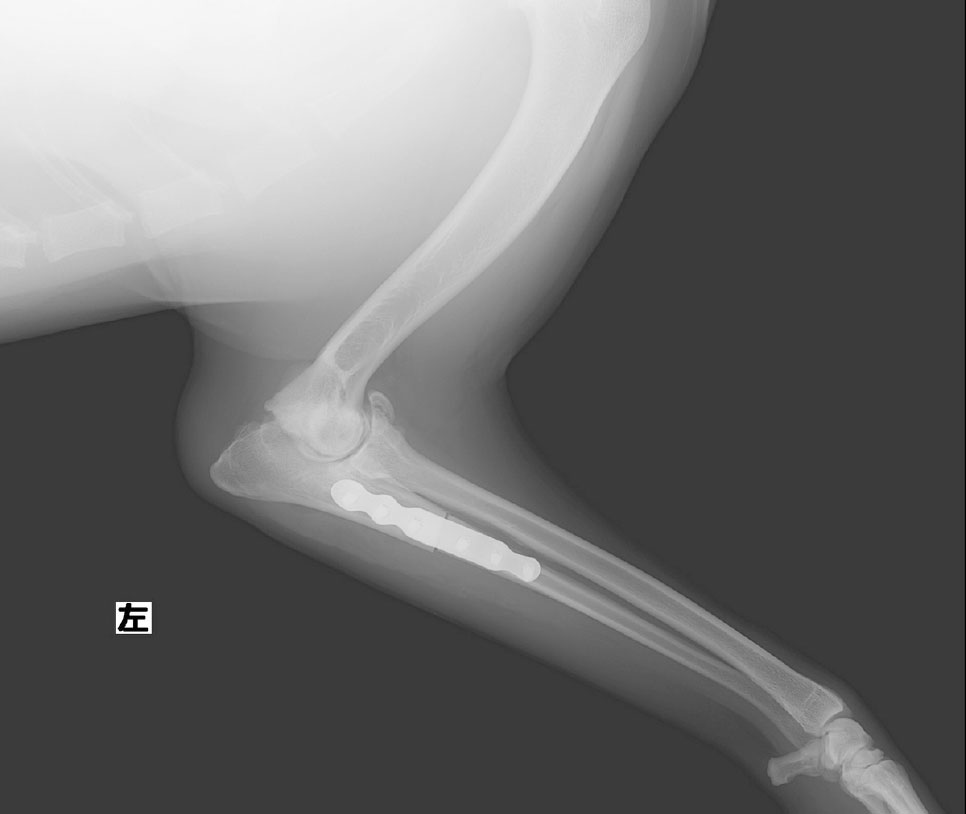

近位尺骨外反骨切り術

前肢尺骨を骨切りして角度を矯正、荷重バランスを均等に。

PAUL法では尺骨を特殊な角度で骨切りし、肘関節の内側と外側に均等に荷重がかかるよう、専用の金属板と骨ネジで固定して角度矯正を行います。軟骨は一度消失すると再生されないので、外側の軟骨に損傷が起こる前に手術を行う必要があります。

肘関節の接触力学が内側に崩れて傾いた尺骨の近位(肘付近)を骨切りし、角度の偏りをなくすことで荷重バランスを均衡化させます。術前・術後を比較すると、上腕骨側からの負荷が内側に逃げ、着地の際の反力も受け止められていない状態から、力の受け渡しが中心軸に沿って正しく行われるようになっているのがわかります。